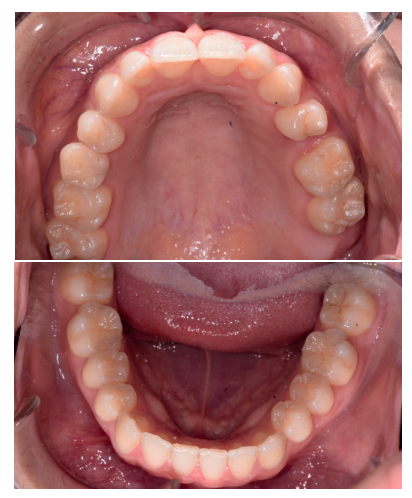

Caso clínico: se presenta un caso clínico de una mujer de 20 años, sin antecedentes médico-quirúrgicos de interés, que acudió a consulta remitida por su ortodoncista, para la extracción de un premolar maxilar retenido, en posición invertida. Tras la extracción del premolar y del tercer molar inferior retenidos, se obtuvo dentina procedente de ambos, para la regeneración ósea guiada del defecto resultante de la extracción del premolar, realizando revisiones a la semana y a los 4 meses de la intervención.

Clinical case: a clinical case of a 20-year-old woman is presented, with no interesting medical record, who went to dental clinic for removal of an inverse maxillary bicuspid retained. After maxillary bicuspid and lower third molar extractions, autogenous dentin was obtained from both teeth, to perform a guided bone regeneration of the bicuspid defect. A week and 4-month check-up were carried out.